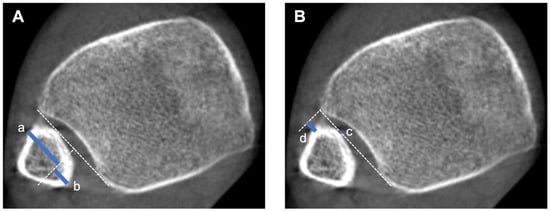

| Fibular rotation by Dikos (α) | The angle between the fibular axis and the tangential line to the anterior and posterior tibial tubercles. A higher angle value indicates internal rotation of the fibula, while a lower angle value indicates external rotation. | [5,13,20,22,26,28,29,31,33,36] |

| Ratio A/B | The ratio between the anterior tibiofibular width (A) and posterior tibiofibular width (B). The ratio increases as the fibula externally rotates. | [5,20,28] |

| Anteroposterior translational ratio by Nault | This is a three-step measurement. A line is drawn between the most anterior and most posterior points of the incisura. A perpendicular line is drawn in the middle of the first line. The distance between the anterior part of the fibula and the perpendicular line is the distance A. B is the distance between the posterior part of the fibula and the perpendicular line. The ratio A/B represents a description of the anteroposterior position. | [5,20,28] |